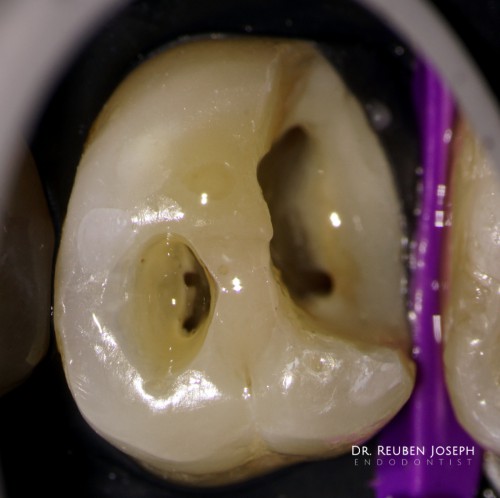

#13 – Caries Driven Access

– Sub-gingival caries distal to an isolated #13 – Gingivectomy and isolation done – Caries […]